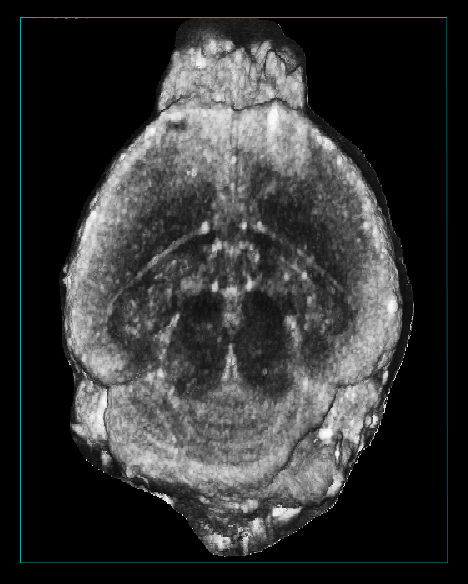

Mouse brain